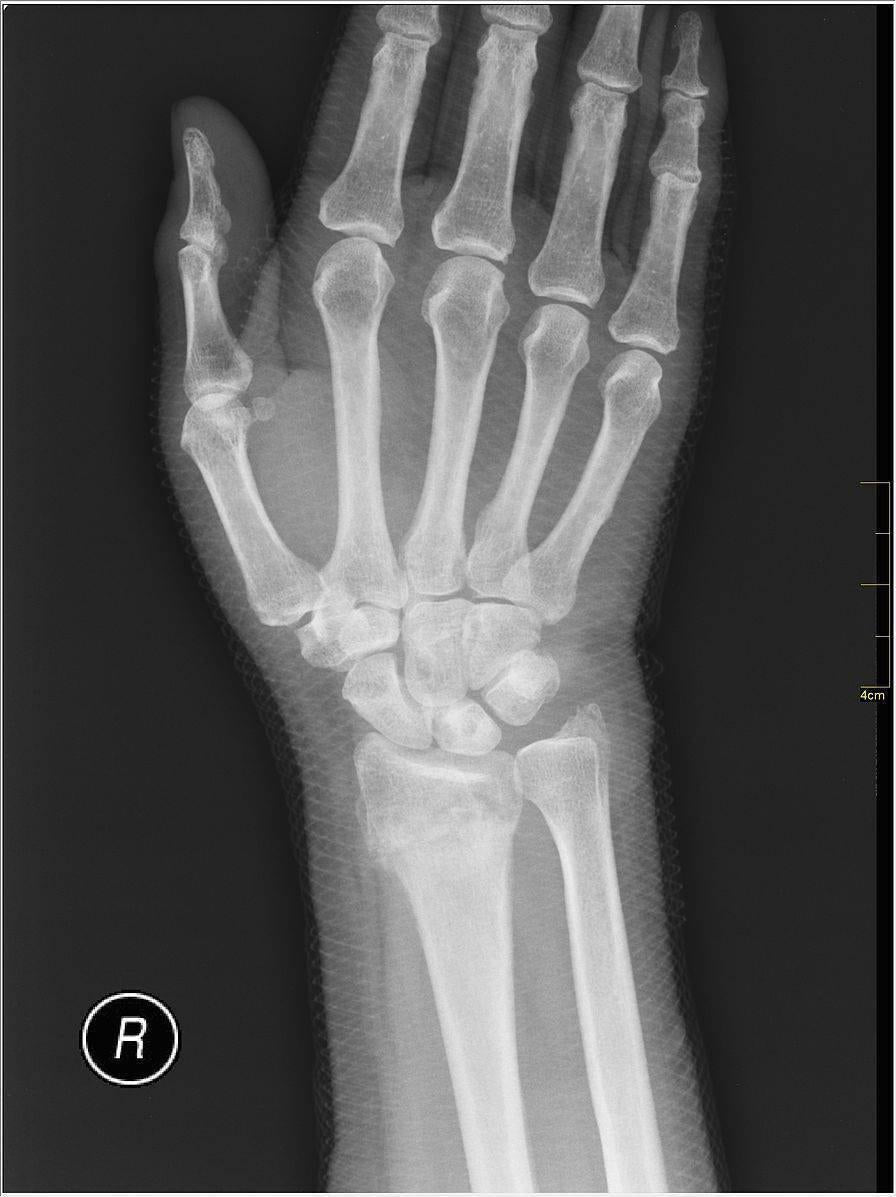

| Distal Radius Fracture Orthopaedic Trauma Association Ota |